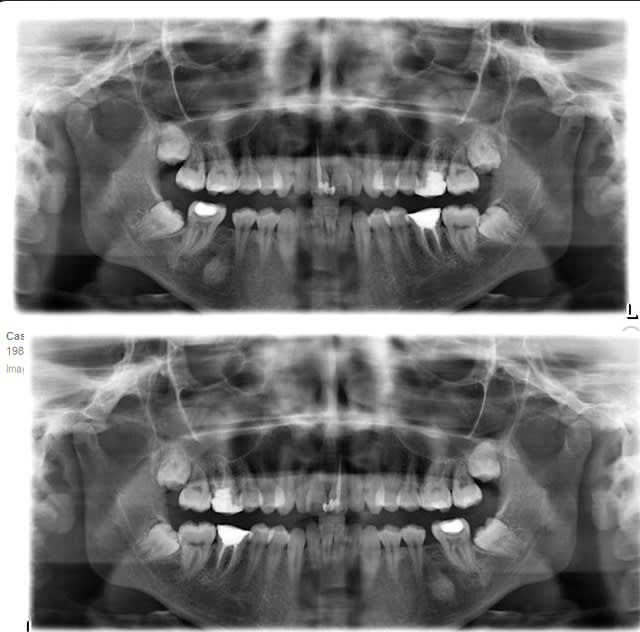

La pano montre des tetes condyliennes usées, une tomo des ATM. nous donnera plus de renseignements

Personnellement je ne vois aucun signe particulier d’usure, les têtes condyliennes m’apparaissent tout à fait normales

Je me suis amusé d’autre part à retourner la panoramique pour comparer les deux coté et objectiver une éventuelle différence de morphologie des deux condyles (image ci-dessous). Il n’y en a quasiment pas.

Phil l’a bien dit : panoramique = tomo.